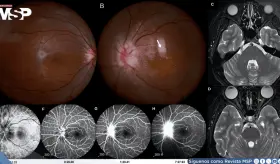

La paciente, quien había adoptado un gato callejero seis meses antes, consultó por disminución visual aguda del ojo izquierdo con escotoma central de una semana de evolución.